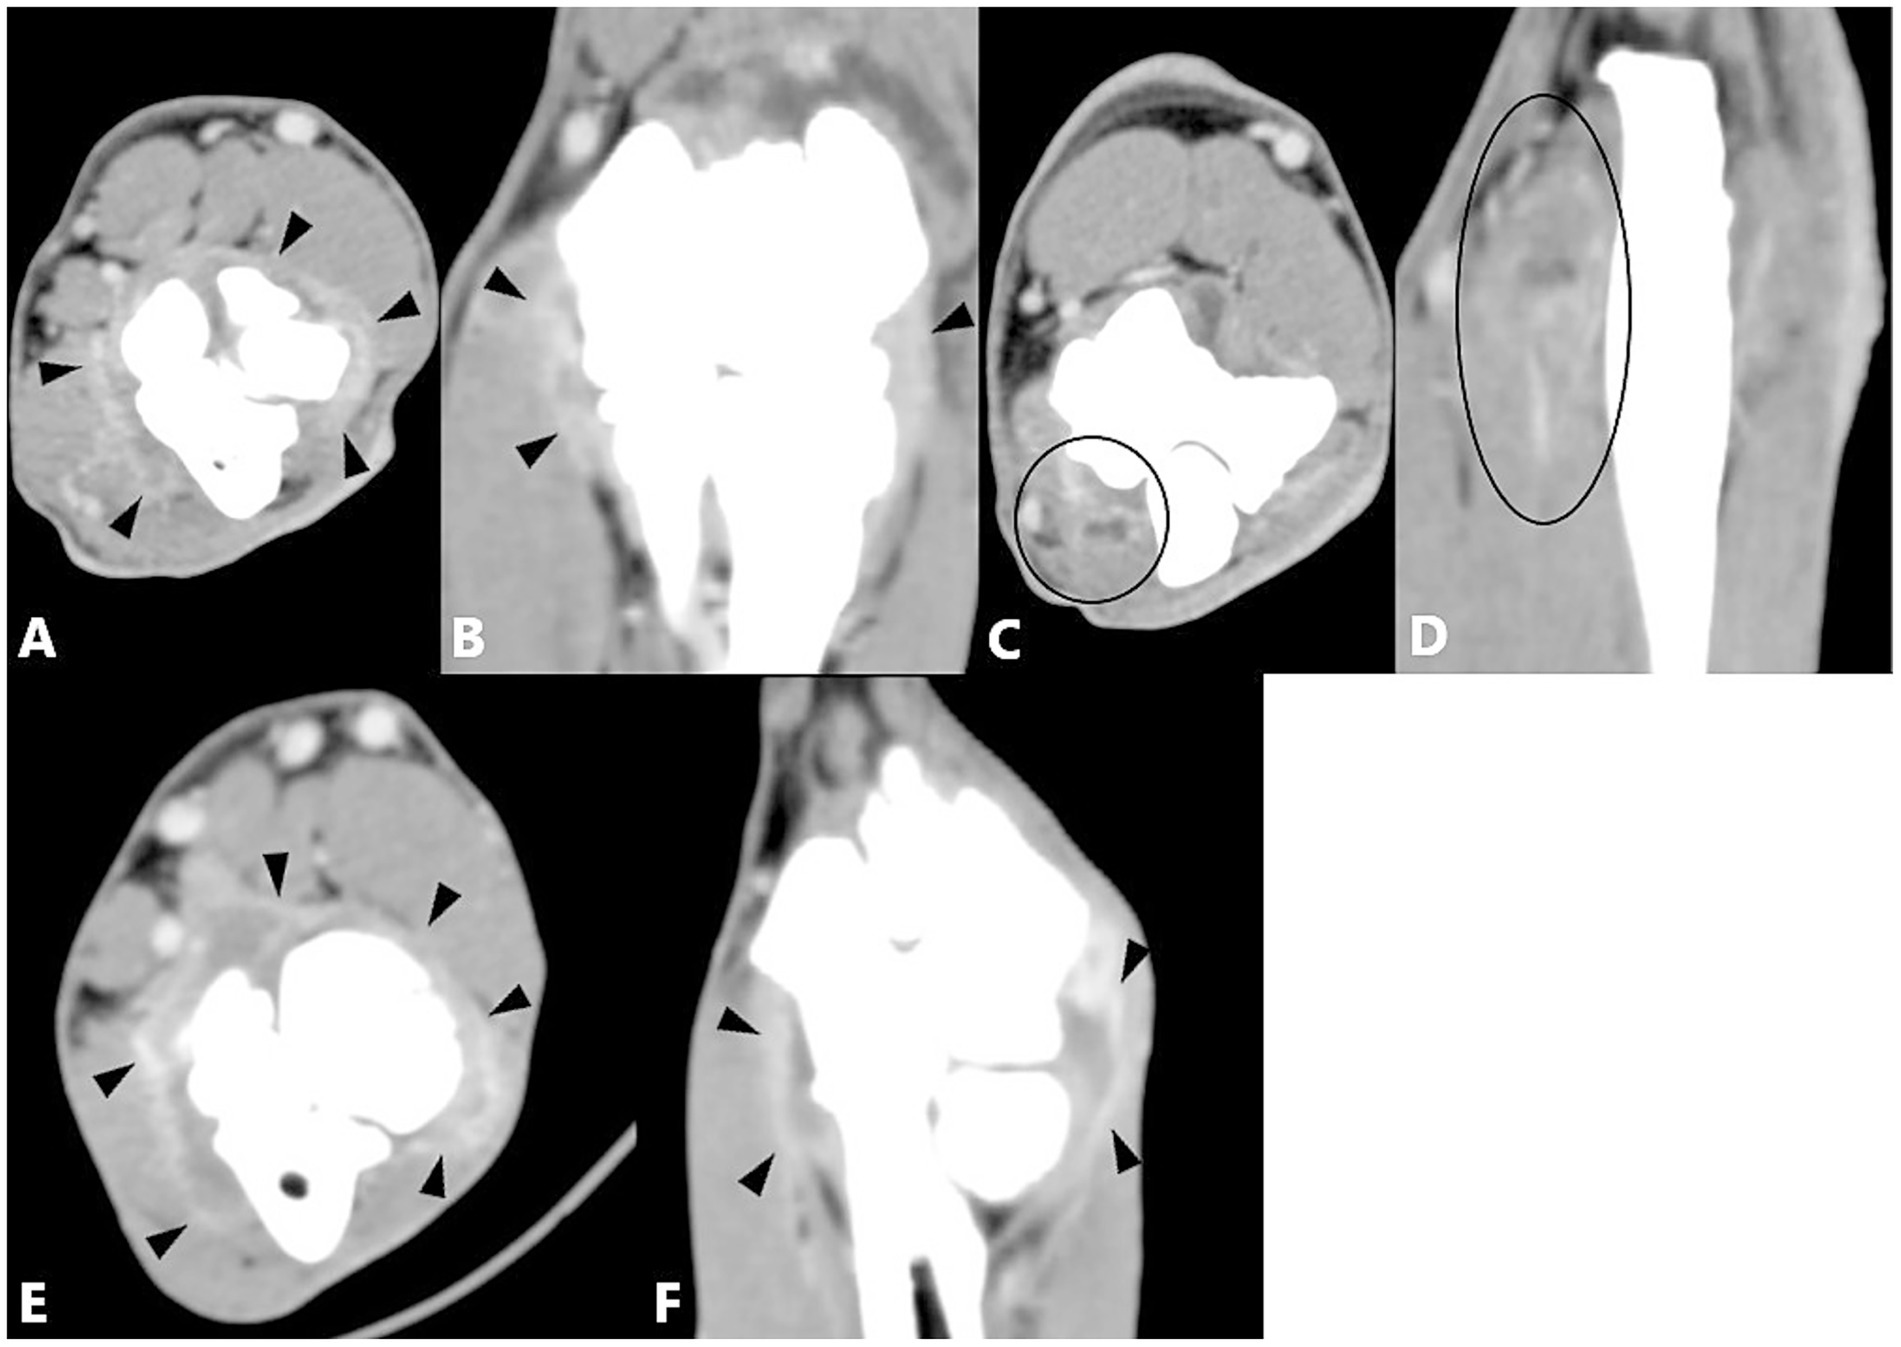

The combination of MCPD and an epicondylar spur (n = 23) produced significantly greater enhancement of the joint capsule and flexor muscles compared with the control group. A significant correlation was also observed between joint capsule enhancement and the combination of MCPD and a medial calcified body (n = 4) compared with the control group (Figure 4). No significant difference from the control group was observed for other combinations of two primary diseases, and no statistical significance could be calculated when enhancement was absent or case numbers were insufficient (Table 8).

Figure 4. Computed tomography slices of elbow joints with two primary diseases showing significant correlation with contrast enhancement of the joint capsule and/or flexor muscles. (A,B) Left elbow joint with MCPD and epicondylar spur showing joint fluid and contrast enhancement of the joint capsule (black arrowheads). (C,D) Same joint showing contrast enhancement of the flexor muscles (black circle). (E,F) Left elbow joint with MCPD and medial calcified body showing joint fluid and contrast enhancement of the joint capsule (black arrowheads).

Among the three primary diseases combinations, those involving MCPD, an epicondylar spur, and a caudal calcified body (n = 4), or MCPD, an epicondylar spur, and a medial calcified body (n = 2), showed a correlation with joint capsule enhancement compared with the control group. The combination of MCPD, an epicondylar spur, and a caudal calcified body also showed a significant association with flexor muscle enhancement compared with the control group (Figure 5). No significant differences were observed for other three primary diseases combinations, either due to the absence of enhancement or insufficient case numbers. Enhancement of both the joint capsule and flexor muscles was observed in a single elbow joint with four primary diseases, but statistical significance could not be determined (Table 9).

Figure 5. Computed tomography slices of elbow joints with three primary diseases showing significant correlation with contrast enhancement of the joint capsule and/or flexor muscles. (A,B) Left elbow joint with MCPD, epicondylar spur, and a caudal calcified body showing contrast enhancement of the flexor muscles (black circle). (C,D) Same joint showing increased joint fluid and contrast enhancement of the joint capsule (black and white arrowheads). The dorsal reconstruction (D) also shows contrast enhancement of the flexor muscles (black circle). (E,F) Left elbow joint with MCPD, epicondylar spur, and a medial calcified body showing joint fluid and contrast enhancement of the joint capsule (black arrow heads).